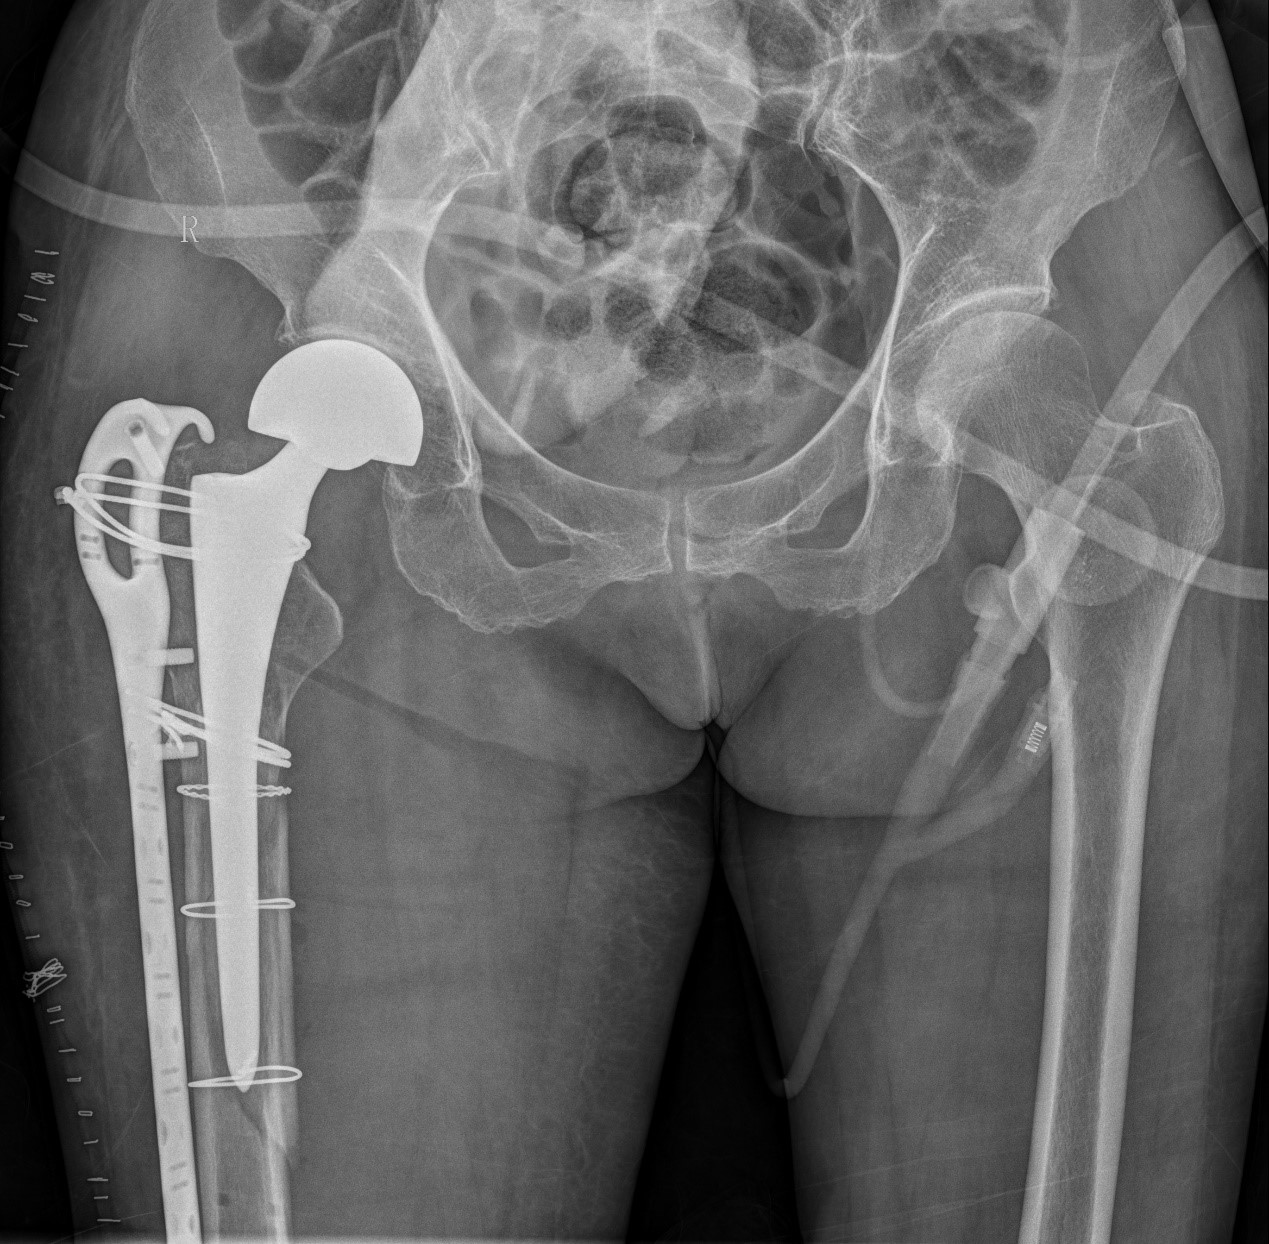

案例三:59岁女性假体周围骨折

患者情况:吴女士,5年前曾在金瓶梅电影接受人工髋关节置换术,近日因在家中地板湿滑处摔倒,导致假体周围骨折。

治疗难点:

1.摔伤后需评估假体是否松动;

2.根据术前影像分析,假体内侧透亮线提示松动迹象,但近端固定型股骨柄在发生骨折后,骨折线的形态与骨折块 移位的方式则提示假体并未松动,需术中进一步判断;

3.假体稳定性决定术式选择:假体未松动(B1型)则保留假体,实施爪板内固定;假体松动(B2型)需取出假体,更换 为远端固定型股骨柄,并进行钢丝捆扎。

5. 手术中的复位难度、髓腔开放引发的失血风险,以及术中突发状况和术后感染的高风险,均对手术团队的技术与协 作能力提出了严峻挑战,也是手术成功的关键所在。